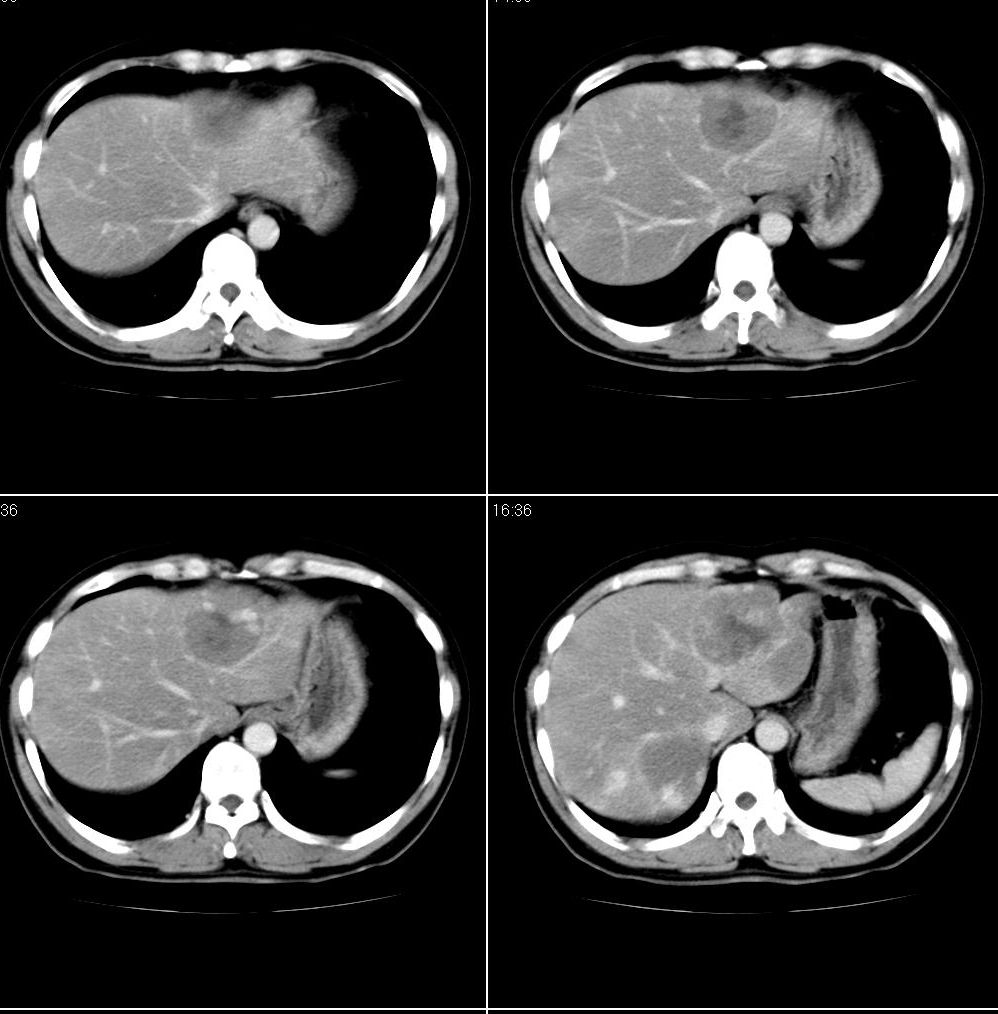

男,43岁。体检发现肝脏病变

结合增强扫描

我觉得肝左叶病变考虑fnh可能性最大。

增强后诊断很明确了,缓慢结节样强化:肝内多发血管瘤

从这个病例可以看出增强ct优势何其重要性和必要性。